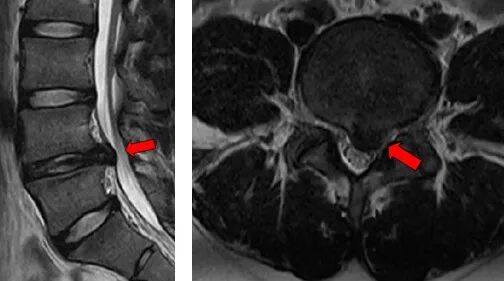

核磁共振提示腰4/5椎間盤向左后方脫垂,左側(cè)L5神經(jīng)根明顯受壓

為了進一步治療,小陳以“腰4/5椎間盤突出癥”辦理了住院手續(xù)。脊柱外科醫(yī)療團隊展開病情討論,認為患者為青少年,腰4/5椎間盤向左后方脫垂,左側(cè)L5神經(jīng)根明顯受壓,患者下肢疼痛明顯,嚴重影響正常生活和學(xué)習(xí),可在硬膜外麻醉下行椎間孔鏡下腰4/5椎間盤摘除術(shù),以解除神經(jīng)壓迫。